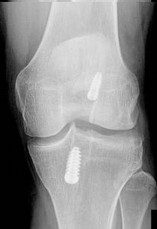

Question 16:

A 19-year-old football player undergoes primary anterior cruciate ligament (ACL) reconstruction using a bone-patellar tendon-bone (BPTB) autograft. In comparing the biomechanical properties of the graft to the native ACL, which of the following statements is true regarding stiffness?

Options:

- The BPTB graft is significantly less stiff than the native ACL

- The BPTB graft has equivalent stiffness to the native ACL

- The BPTB graft is approximately 3 to 4 times stiffer than the native ACL

- A quadrupled hamstring graft is less stiff than the native ACL

- The native ACL is structurally stiffer than all available autograft choices

Correct Answer: The BPTB graft is approximately 3 to 4 times stiffer than the native ACL

Explanation:

The native ACL has a stiffness of approximately 242 N/mm. A 10-mm BPTB graft has a stiffness of approximately 620 N/mm (some studies cite up to 3x, or ~730 N/mm depending on exact width and testing parameters), making it significantly stiffer than the native ACL. A quadrupled hamstring graft is even stiffer, typically around 800 N/mm.